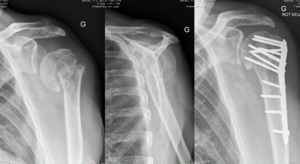

| − | Treatment of a chronic nonunion of the proximal humerus in the elderly should be treated with fixation when possible. Critical attention should be paid to correct all deformities: tuberosity positioning, articular surface realignment, soft tissue balancing, and treatment of soft tissue contractures. Attempts at anatomic total shoulder arthroplasty have failed. Reverse shoulder arthroplasty is generally recommended when the fracture has eroded enough to prevent successful fixation, if the tuberosities have resorbed, if the rotator cuff is torn, or other findings are present that would limit the success rate of fixation. | + | Treatment of a chronic nonunion of the proximal humerus in the elderly should be treated with fixation when possible (Figure). Critical attention should be paid to correct all deformities: tuberosity positioning, articular surface realignment, soft tissue balancing, and treatment of soft tissue contractures. Attempts at anatomic total shoulder arthroplasty have failed. Reverse shoulder arthroplasty is generally recommended when the fracture has eroded enough to prevent successful fixation, if the tuberosities have resorbed, if the rotator cuff is torn, or other findings are present that would limit the success rate of fixation. |

| + | [[File:Cure malunion.png|thumb]] | ||